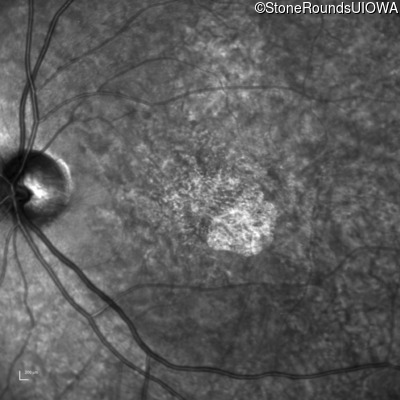

The clinical features favoring the diagnosis of ABCA4-associated autosomal recessive Stargardt disease in this patient include: loss of acuity at the beginning of the second decade, parafoveal photoreceptor loss on OCT, pisciform flecks in the macula with clear peripapillary sparing, and normally sighted parents.

All three of the cardinal ophthalmic features of Mendelian macular dystrophies are present in this patient. The most striking features of the fundus exam are the numerous yellow flecks at the level of the RPE. Flecks are most commonly seen in AR Stargardt disease and pattern dystrophy although they may be seen in some of the rarer Mendelian maculopathies as well. The visual acuity in patients with AR Stargardt disease is often "worse than the fundus looks" while the acuity in pattern dystrophy is often quite good despite extensive flecks. The pedigree of this patient is compatible with ABCA4-associated Stargardt disease and the better than expected acuity is attributable to foveal sparing (see below). The onset of reduced acuity at age 10 is much more characteristic of ABCA4 disease than pattern dystrophy. Another feature present in this patient that is very frequently seen in Stargardt disease is peripapillary sparing. However, this sign can be seen in pattern dystrophy as well. When central atrophy is present in ABCA4-associated Stargardt disease it often somewhat shiny (which is uncommon with the geographic atrophy of pattern dystrophy or age-related macular degeneration). Some patients with ABCA4-associated Stargardt disease can have some preservation of the fovea giving a zonal "bullseye" appearance to the center of the macula. Sometimes this preservation is associated with preserved acuity as in this case. The outer nuclear layer (ONL) is much thinner than normal on OCT, indicative of photoreceptor loss. This is associated with a thinning of the ellipsoid zone which is usually many times brighter and thicker than the external limiting membrane (ELM). These two lines are essentially equal in intensity in this patient. The foveal sparing is seen on OCT only as a small bit of retinal convexity in the center of the atrophy coupled with a small bit of residual RPE flanked by bare Bruch's membrane. The presence of a robust I2e isopter on Goldmann perimetry places this patient in the least severe half of all Stargardt patients (see Schindler, et al., 2010). Most patients with ABCA4-associated disease are somewhat myopic as is this patient. Stargardt patients also tend to perform very poorly on pseudoisochromatic plates, even when their acuity is still fairly good as it is here.